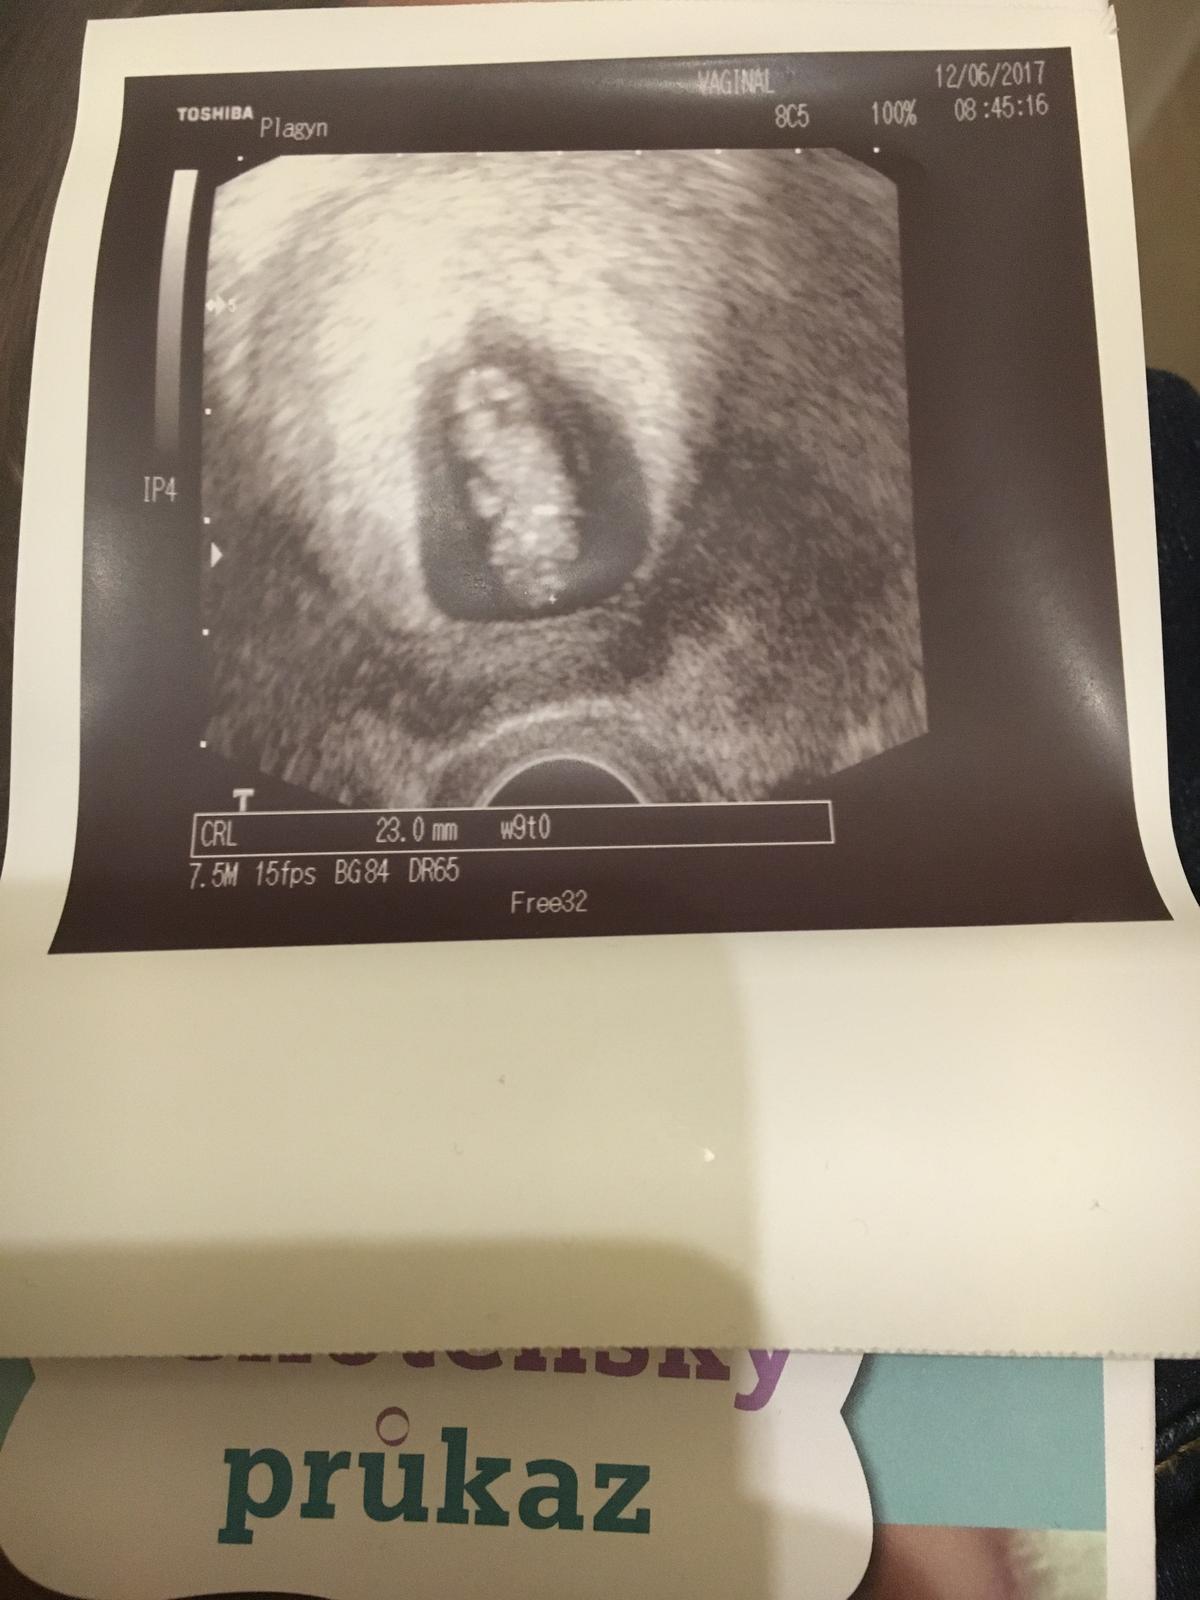

Jinak posílám fotku z dnešní kontroly 🙂

@simi1510 jůůůů, to je mimísek 👶 .... krásná fotka

@simi1510 krásná fotka 👏👏👏 předpokládám, že kontrola proběhla na jedničku 😉

@alli005 je o čtyři dny teď mladší, ale to se snad zase spraví 🙂 jinak jako takove mimi ok

@jullli Jj, jsme domluveni, ze na každé prohlídce bude, aby se ohlídat ten myom a pripadne nejake problemy. Jen nesedí me o 4 dny ted no

@simi1510 to víš že jo, pár dní dopředu nebo dozadu nic neznamená 🙂 mám radost za tebe, že je mimi v pořádku 😉

To vubec nevadi zalezi hodne na utz a podle fotky nema uplne moc dobre rozliseni Takze je mozne ze proste blbe zmeril a hlavne nikdy to nemusi sedet stejne..